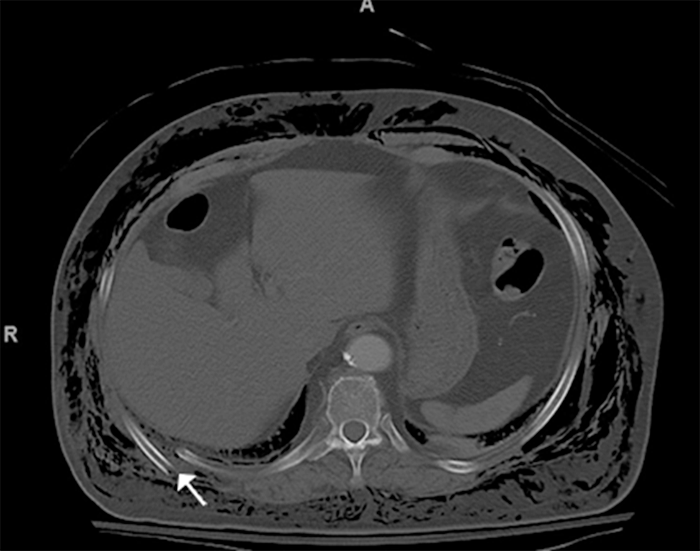

On arrival at our hospital, the patient had severe subcutaneous emphysema. She was hemodynamically normal, saturating 95% on a 3 L nasal cannula. Her imaging revealed comminuted and displaced fractures of right-sided ribs 7 through 9 (Figures 1, 2, and 3).

Figure 2. Comminuted Right Posterior and Lateral 8th Rib Fracture (white arrow). Published with Permission